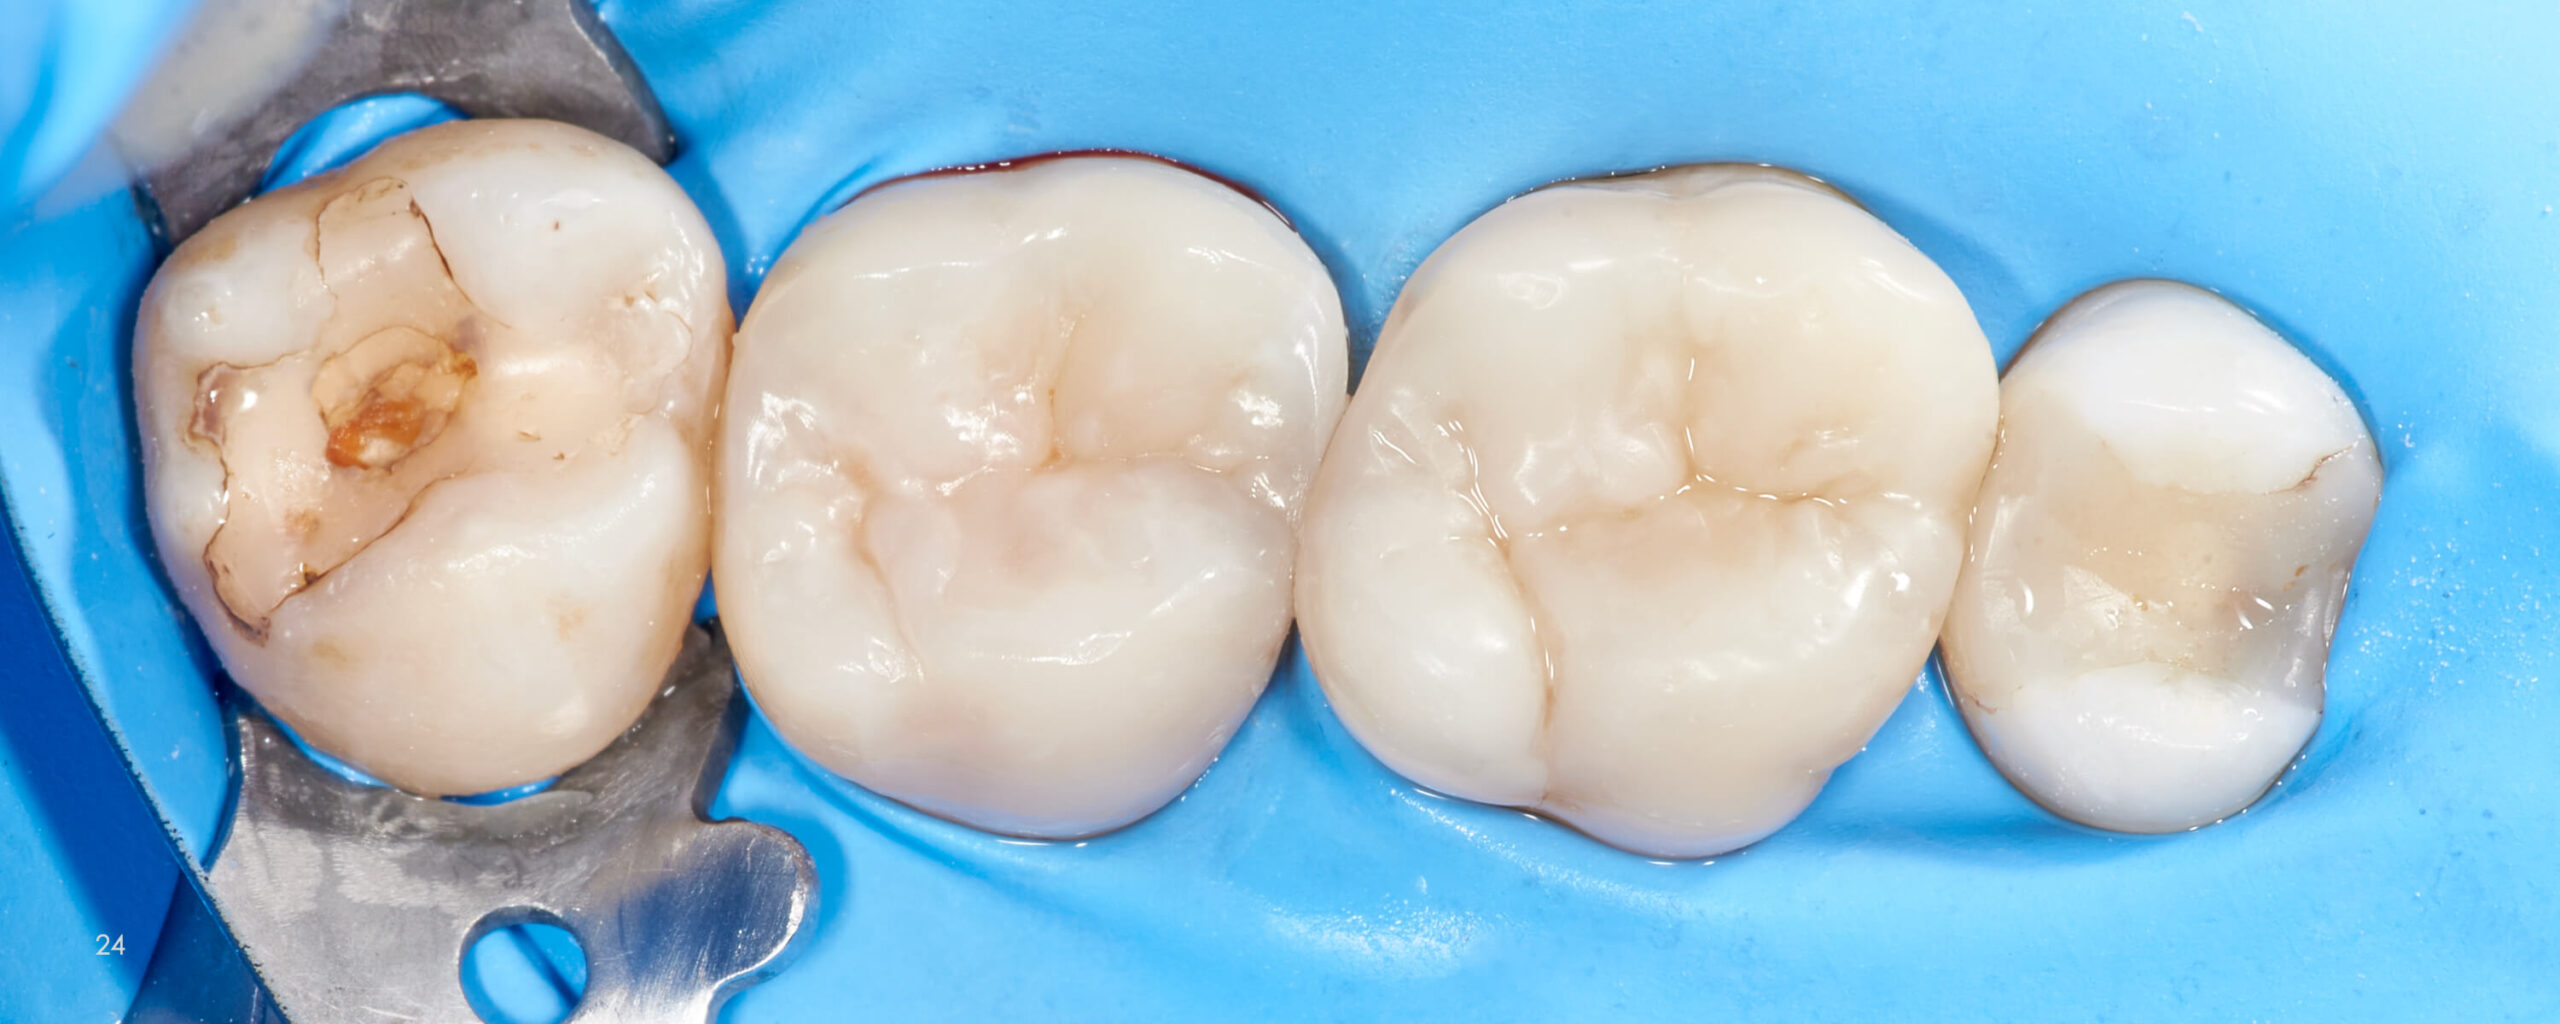

Posterior Teeth Morphology

Direct Composite Restorations

What does the anatomy of natural teeth look like?

How to make a direct overlay restorations?

You’ll find the answers to this and more. After reading this atlas, you will be prepared how to create the biomimetic

restoration using direct method.

This e-book will allow you to avoid a lot of mistakes, save a lot of stress and time during your daily work.